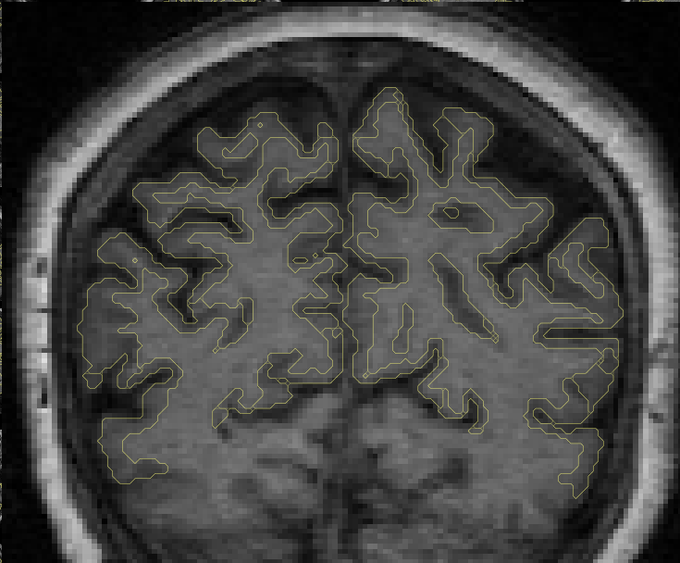

Just learning about SurfIce, looks quite useful: https://t.co/WBsWLGMWlw

More from the Chris Rorden's lab:

https://t.co/tBsw3XLSfe

man, tool discovery is still hard! so many academic "walls" and gaps .. #opensource